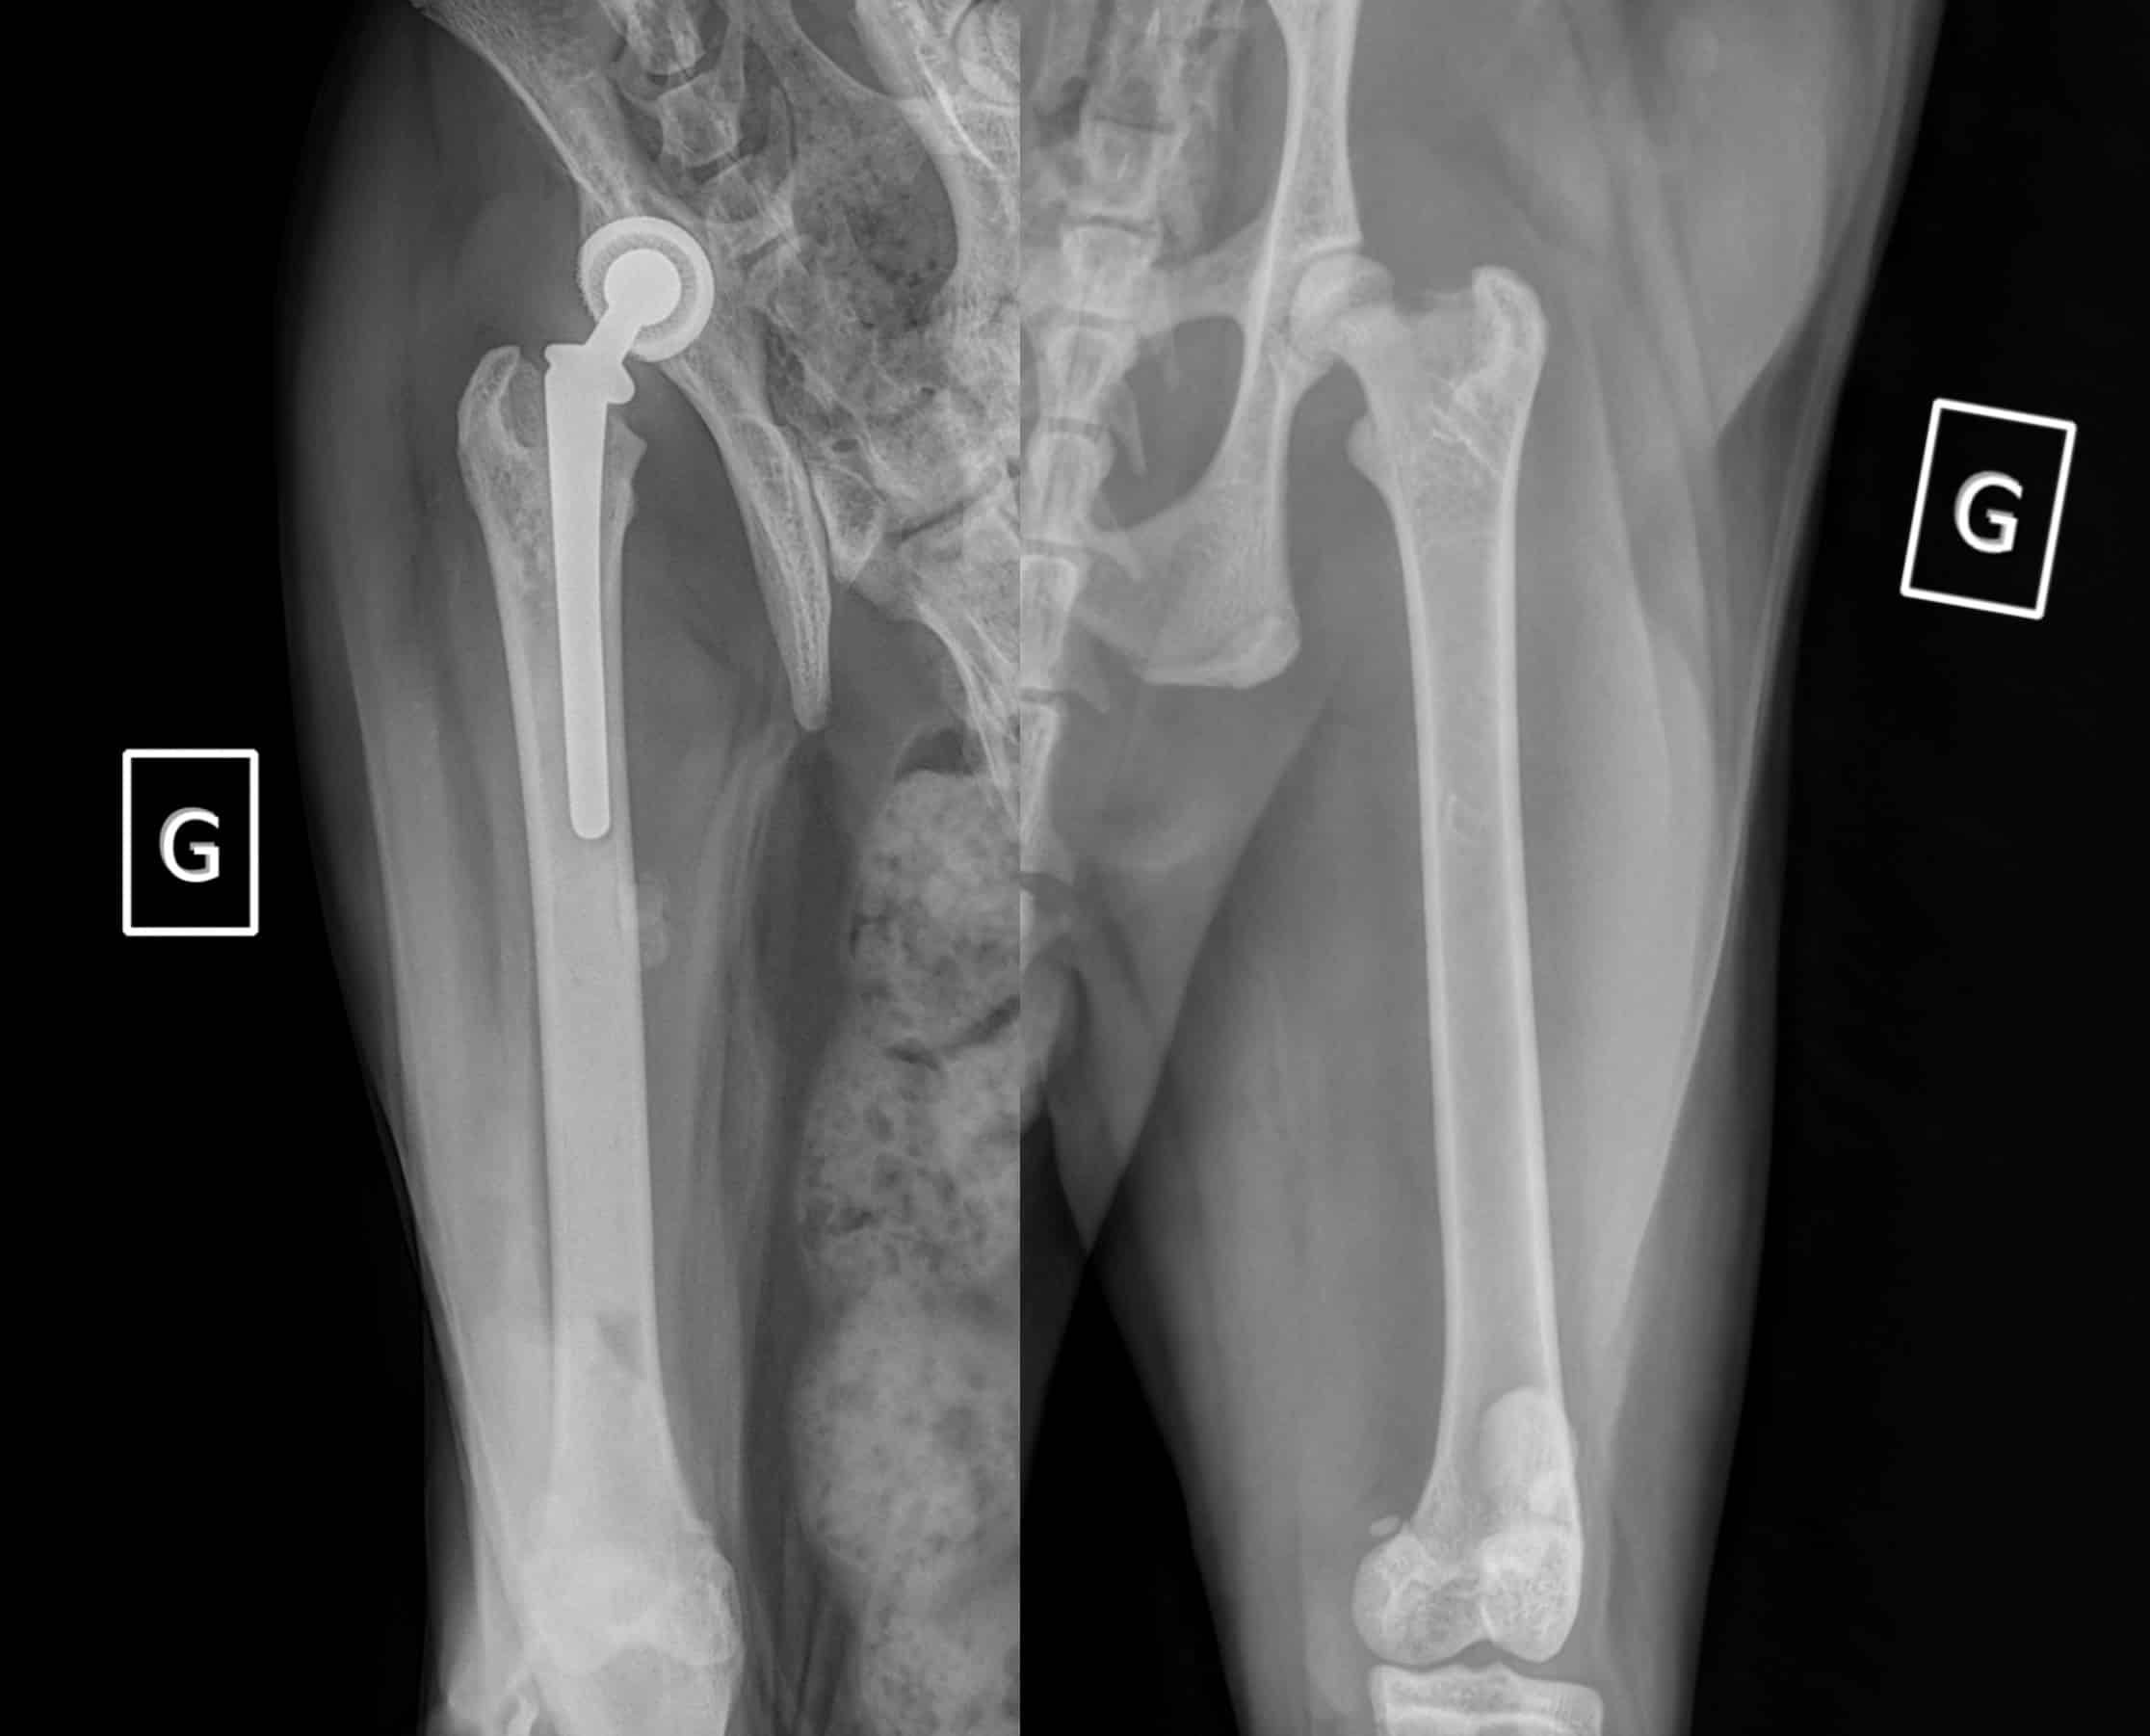

Néanmoins, certaines maladies du jeune ou congénitales sont également rencontrées chez le chat, d’apparition aigue ou progressive, souvent sans traumatisme, parfois associées à des prédispositions raciales : glissement épiphysaire de la tête fémorale, ostéochondrodysplasie du Scottish Fold par exemple. Les chats peuvent également souffrir de dysplasies du coude ou de la hanche, bien que beaucoup moins fréquentes que chez le chien.

A l’hôpital, vous serez reçu par un vétérinaire spécialisé en chirurgie, et même pratiquant exclusivement l’orthopédie. Si possible vous amènerez votre animal à jeun (la boisson est autorisée). Après avoir recueilli les commémoratifs, le vétérinaire examinera votre chat à distance, puis de façon rapprochée. L’examen du chat est plus délicat que celui du chien, ils ont tendance à refuser de se déplacer et à moins se laisser manipuler. Un traitement préalable pourra être prescrit pour les calmer avant la consultation. Le vétérinaire est ensuite susceptible de vous proposer des examens complémentaires (dont certains sous sédation ou anesthésie) tels que des radiographies, ou des ponctions articulaires. Nous disposons d’un service d’imagerie qui peut pratiquer des échographies, un scanner ou une IRM du squelette dans des indications précises mais peu fréquentes. La boiterie peut également nécessiter l’avis d’un neurologue ou d’un oncologue, votre animal sera redirigé vers le service adéquat après une première évaluation par l’orthopédiste, s’il suspecte une cause de cet ordre. Dans la mesure du possible la démarche diagnostique est complétée le jour de la consultation mais il peut arriver de devoir reprendre date. Il en est de même lorsqu’une arthroscopie ou une chirurgie s’avère nécessaire. Dans certains cas, un suivi avec le service de physiothérapie pourra être préconisé suivant la chirurgie ou dans le cadre d’un traitement conservateur.